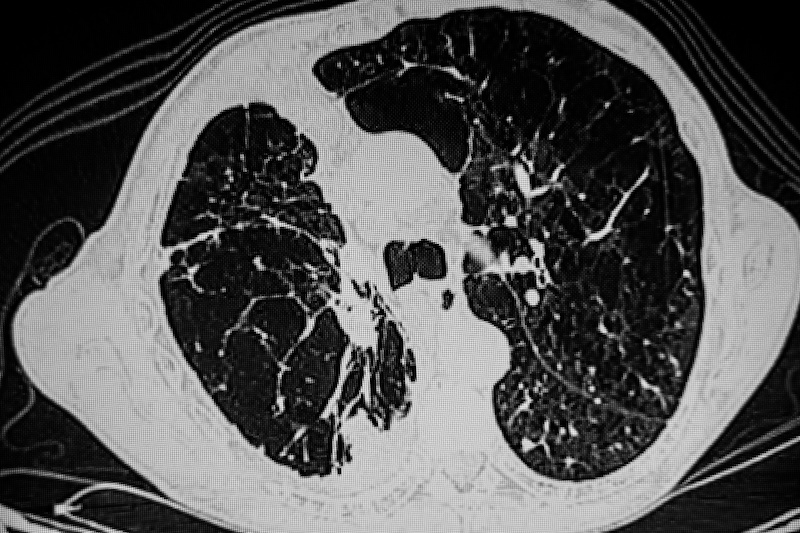

Vienne, Autriche – Deux études présentées lors du congrès 2024 de l'European Respiratory Society (ERS) ont montré d’une part que la tomodensitométrie pourrait aider à mieux orienter les traitements des patients atteints de BPCO et d’autre part que l’analyse des composés organiques volatils dans l'haleine des patients permettrait de mieux prédire les exacerbations.